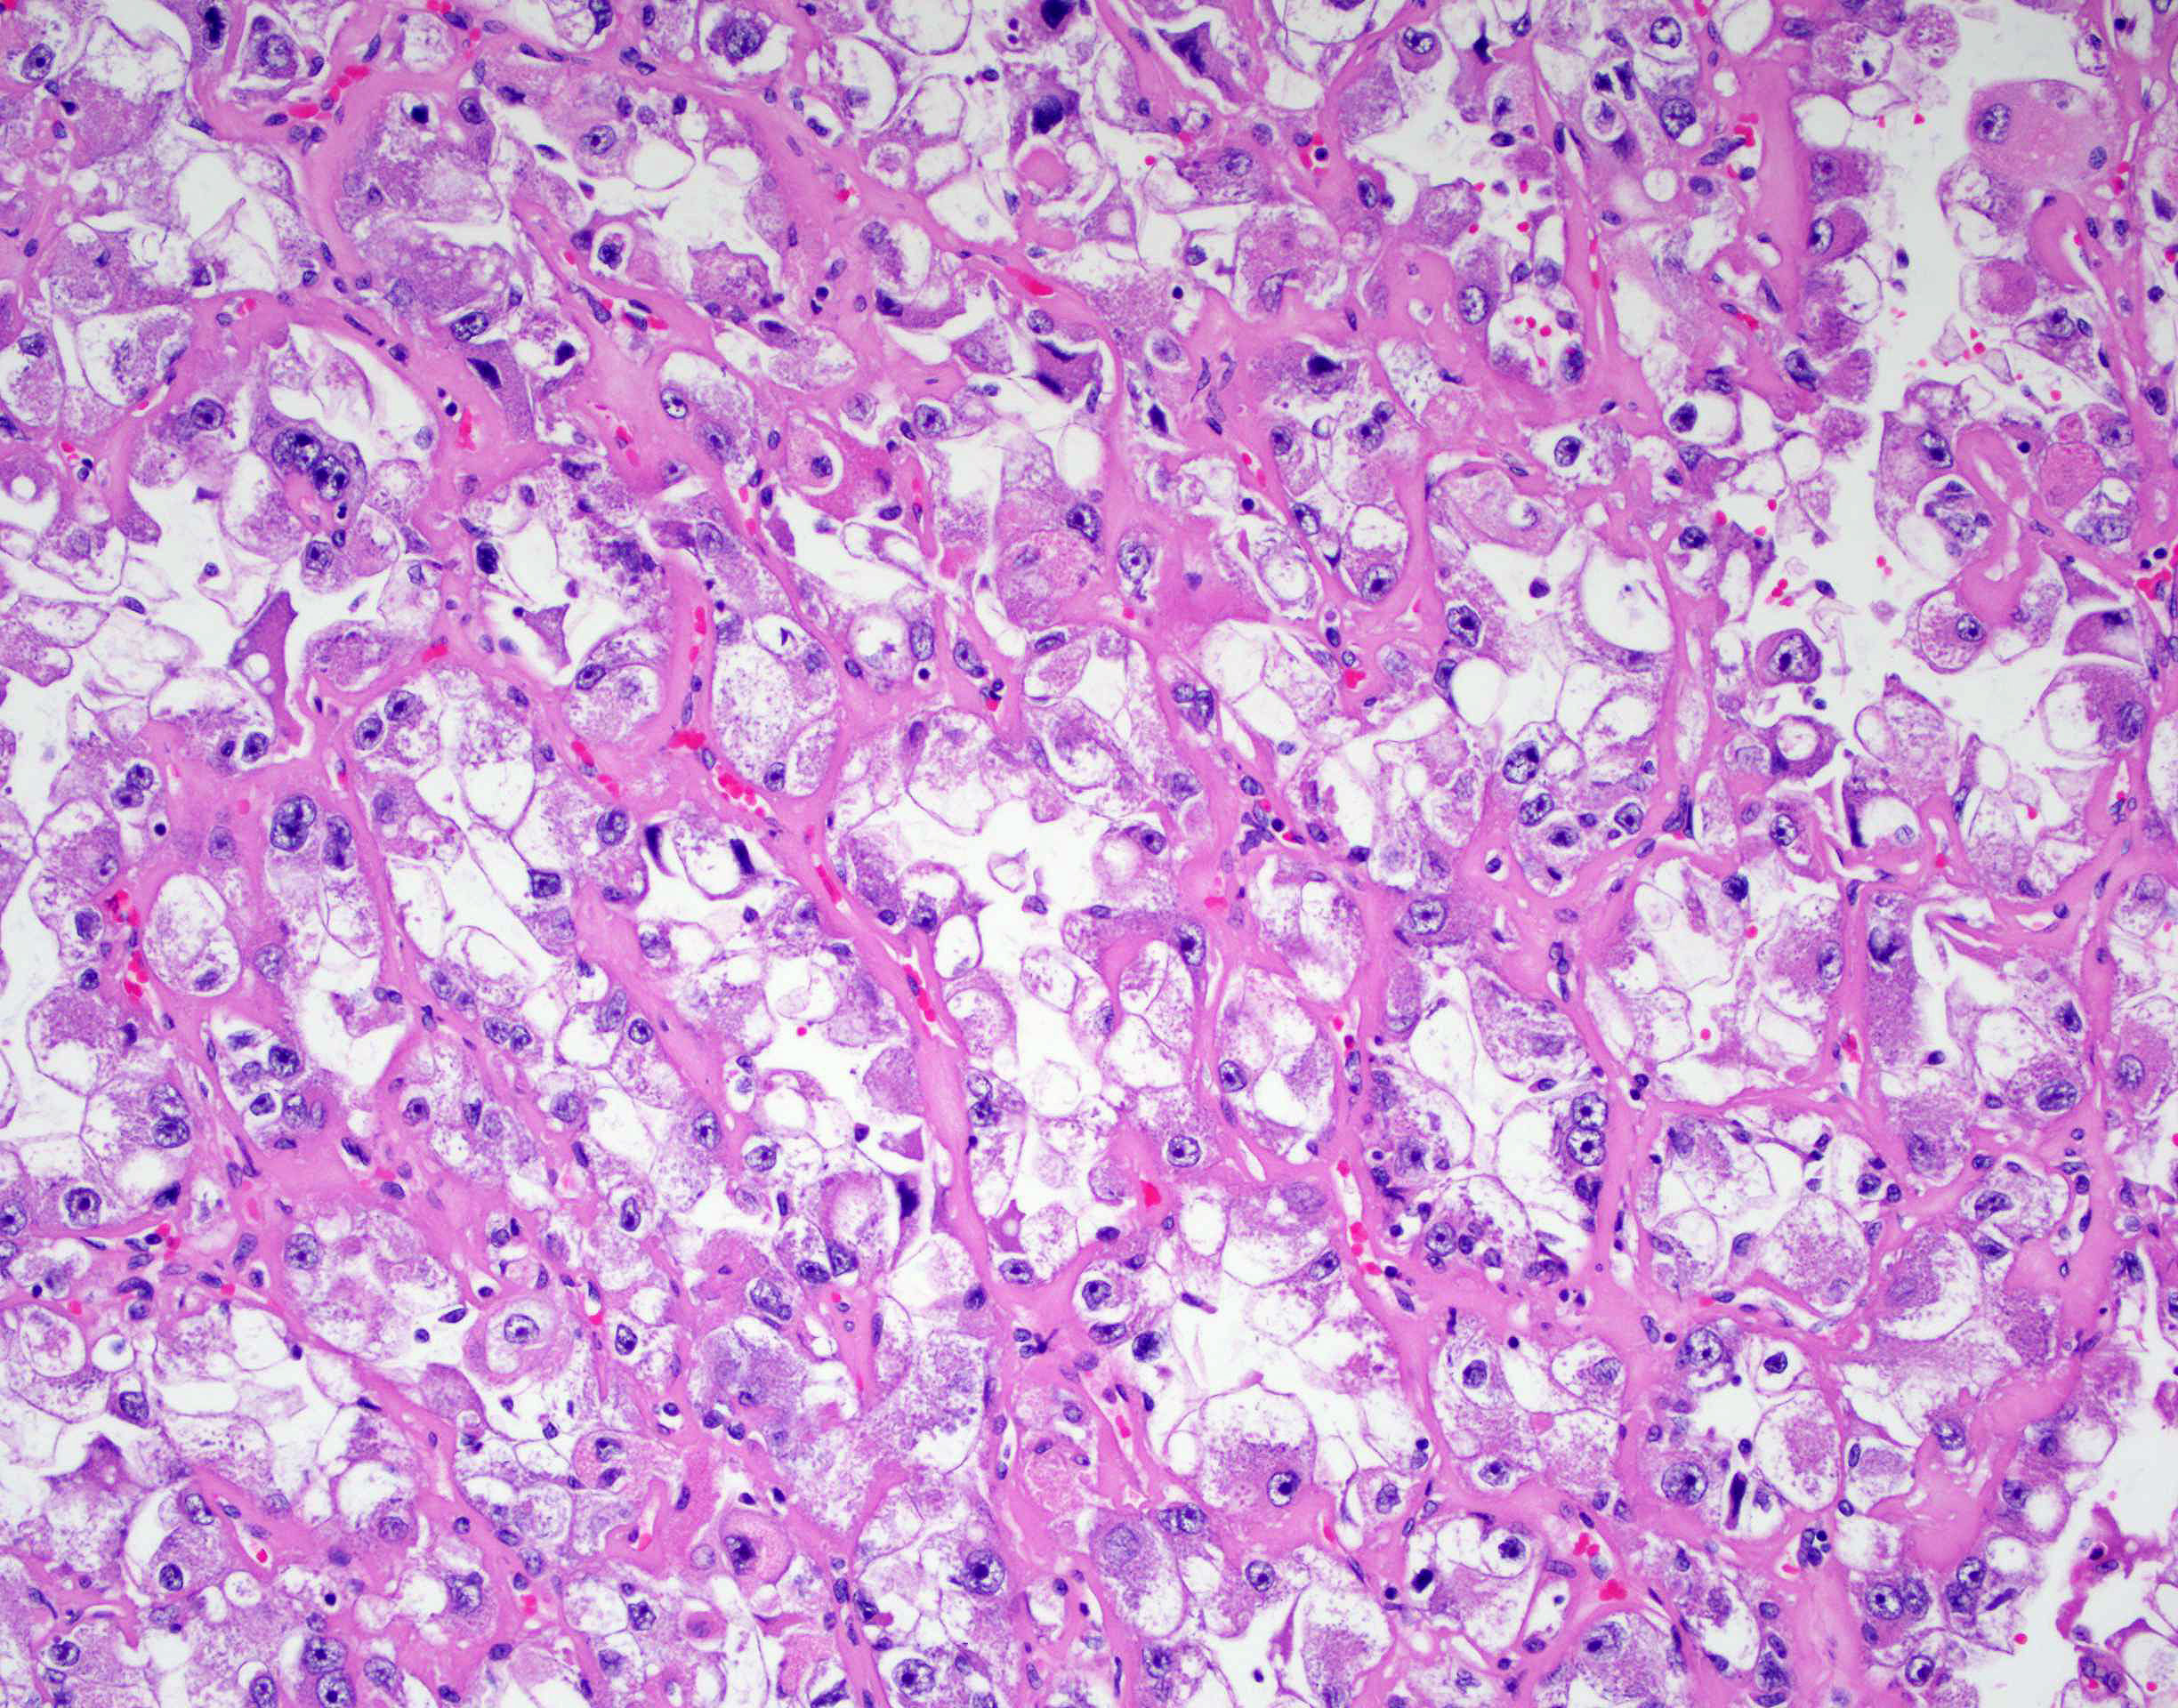

Renal tumor grading

Case ID: 419